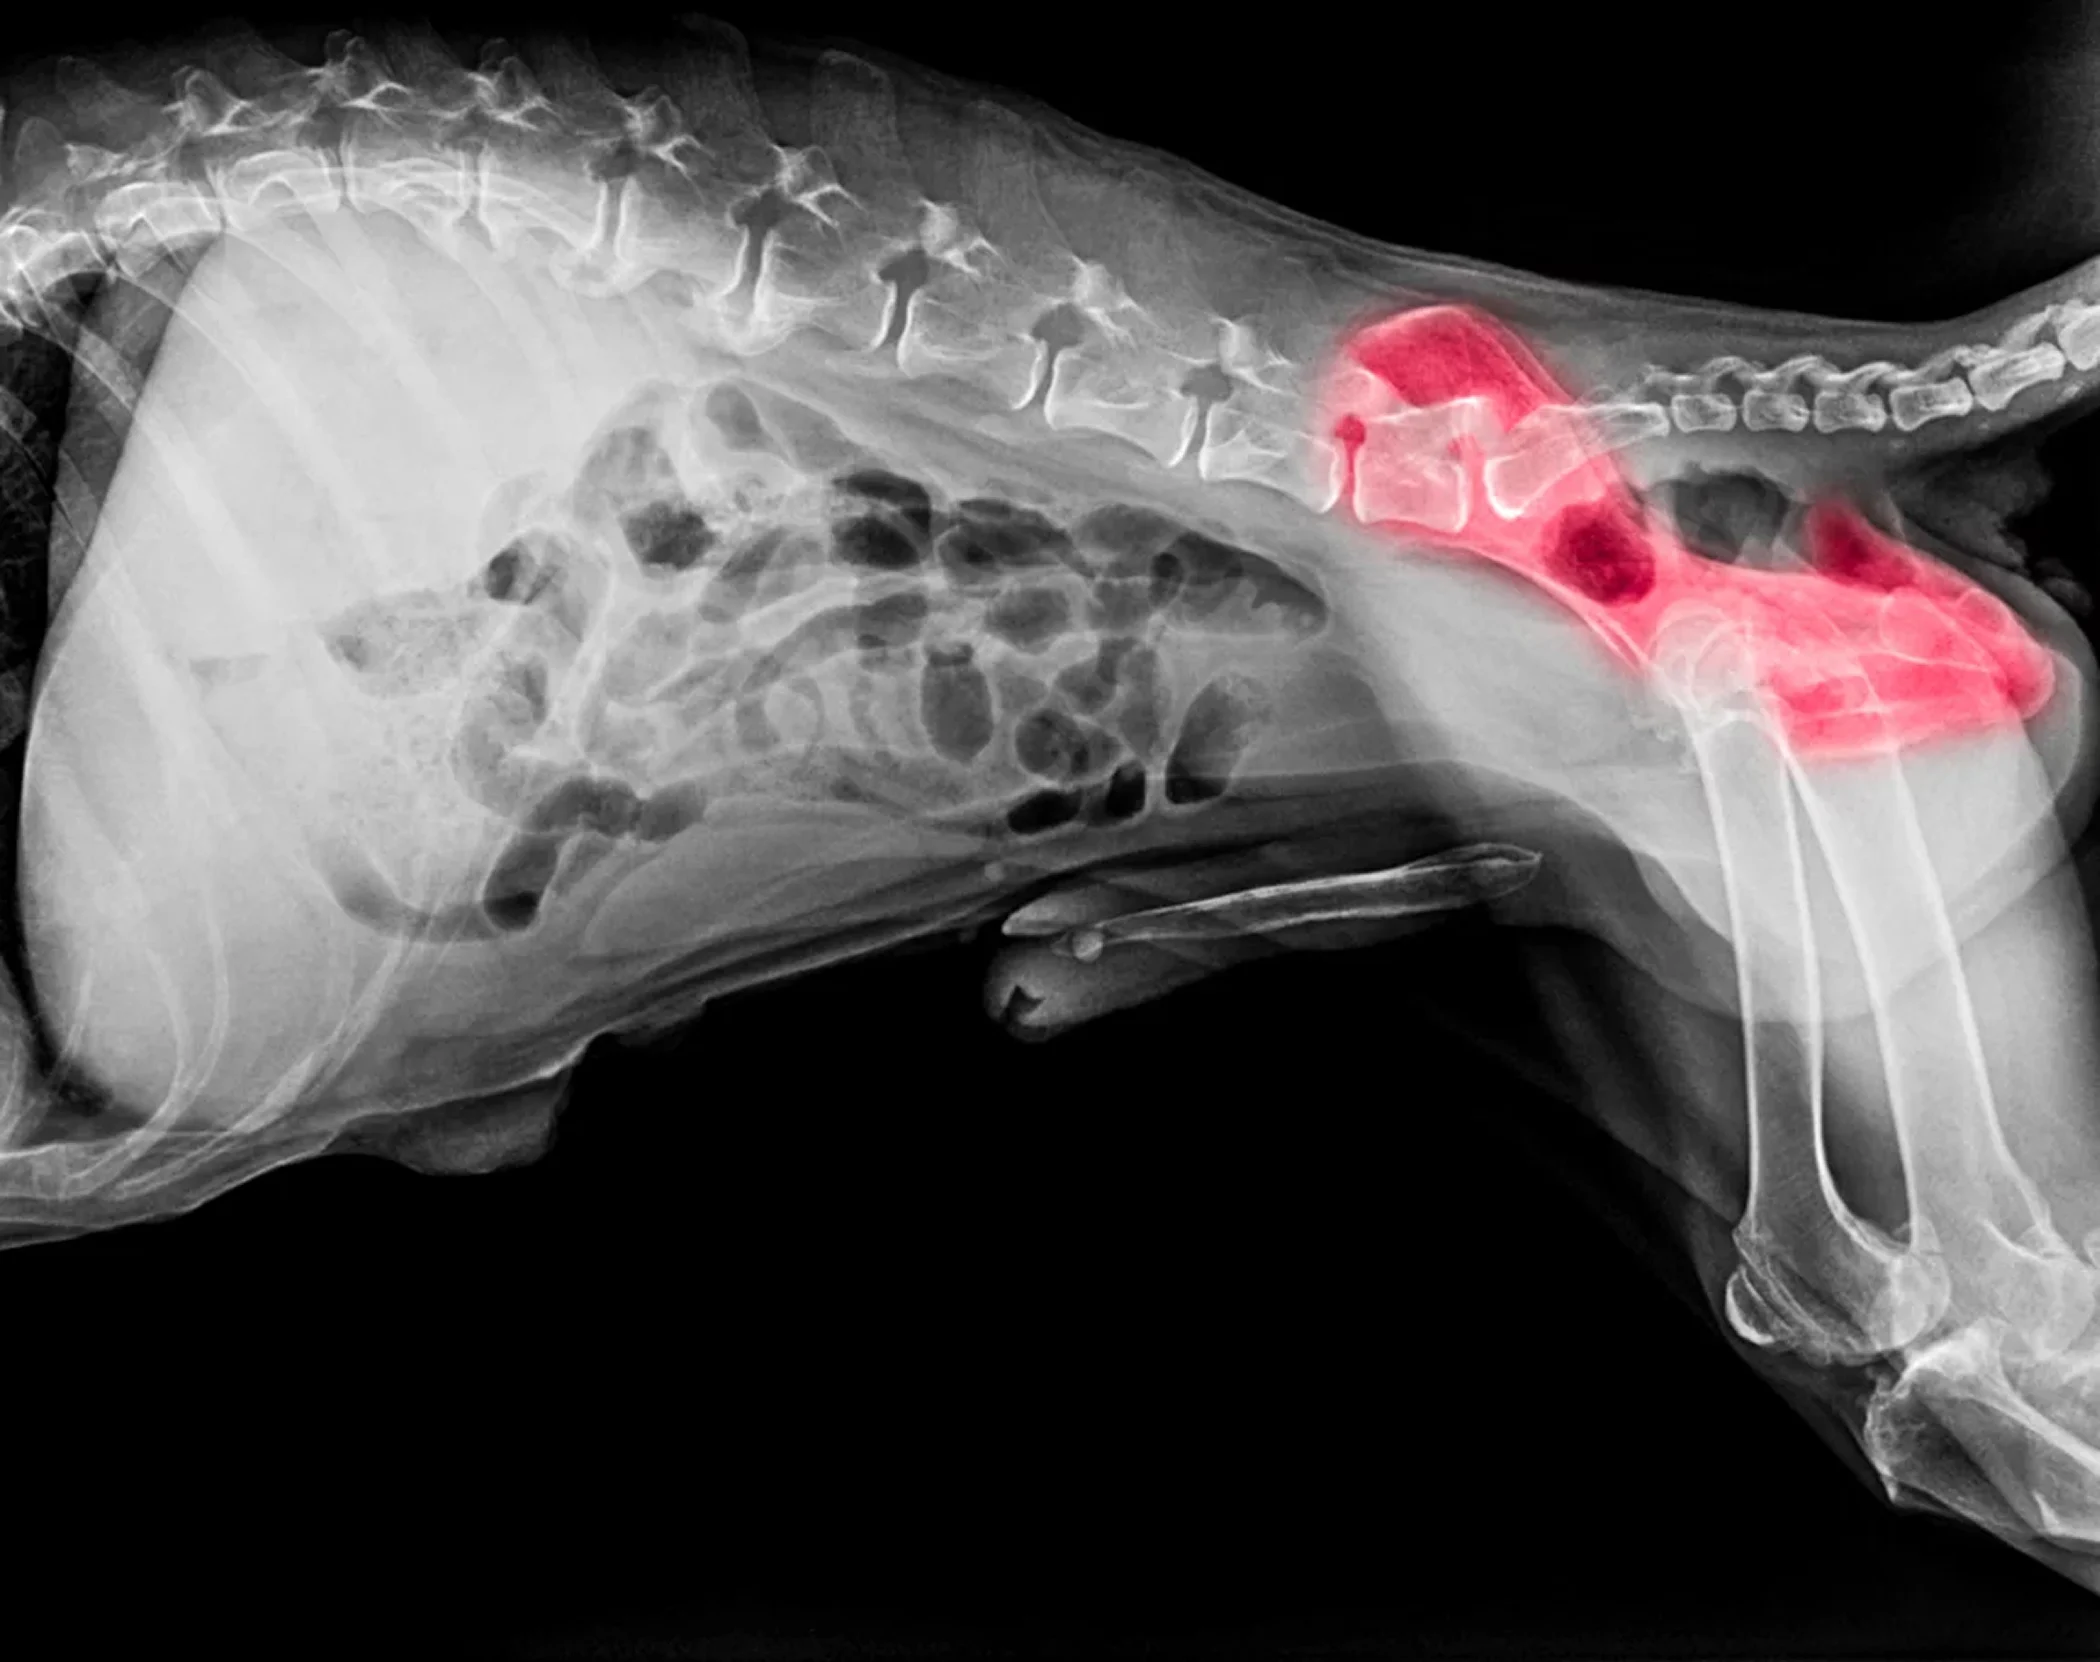

Hip dysplasia isn't just about genetics or bad joint structure…

Yes, those things matter.

But here's what's really causing your dog's pain:

Chronic inflammation is literally destroying their joint fluid.

Think of it like this:

A healthy hip joint is like a well-oiled machine…

There's smooth cartilage cushioning the bones, and synovial fluid lubricating everything so the joint glides effortlessly.

But when hip dysplasia sets in, that loose hip socket creates abnormal friction. And that friction triggers inflammation.

Now here's where it gets worse.

That inflammation doesn't just cause pain…

It actually dries out the synovial fluid.

Like a car engine running without oil, the bones start grinding directly against each other.

The cartilage breaks down…

The pain gets worse…

Which triggers more inflammation...

Which destroys more cartilage and joint fluid.

It's a vicious cycle that gets worse every single day.